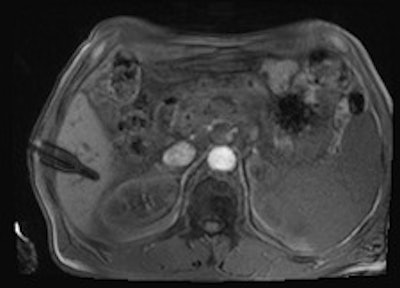

A 50-year-old man with history of pancreatic carcinoma underwent a CT-guided biopsy (above), which was nonconclusive (pathology result: normal liver tissue). Three weeks later, an MR-guided biopsy (below) was performed, and the biopsy revealed a cavernous hemangioma. Images courtesy of Dr. Rüdiger Hoffmann.